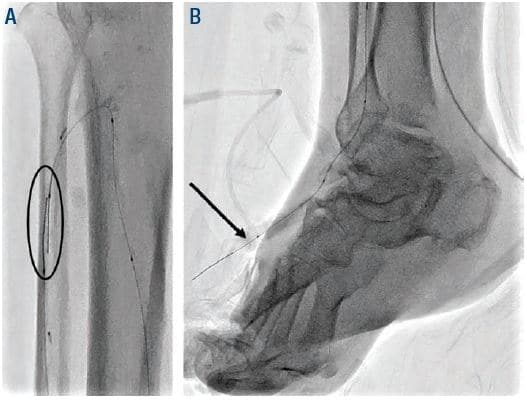

He had a right transradial aortogram with selective right leg angiogram. His angiogram revealed adequate inflow with patent aorto-iliac, common femoral, superficial femoral, profunda, and popliteal vessels. Distally he had a chronically occluded (CTO) right anterior tibial (ATA) with a hibernating dorsalis pedis artery (DPA), which faintly filled from a peroneal (PER) collateral, 90% tibial peroneal trunk (TPT) stenosis, multiple 75% lesions in the proximal and mid posterior tibial artery (PTA), and a patent lateral plantar artery (LPA) (Figure 1).